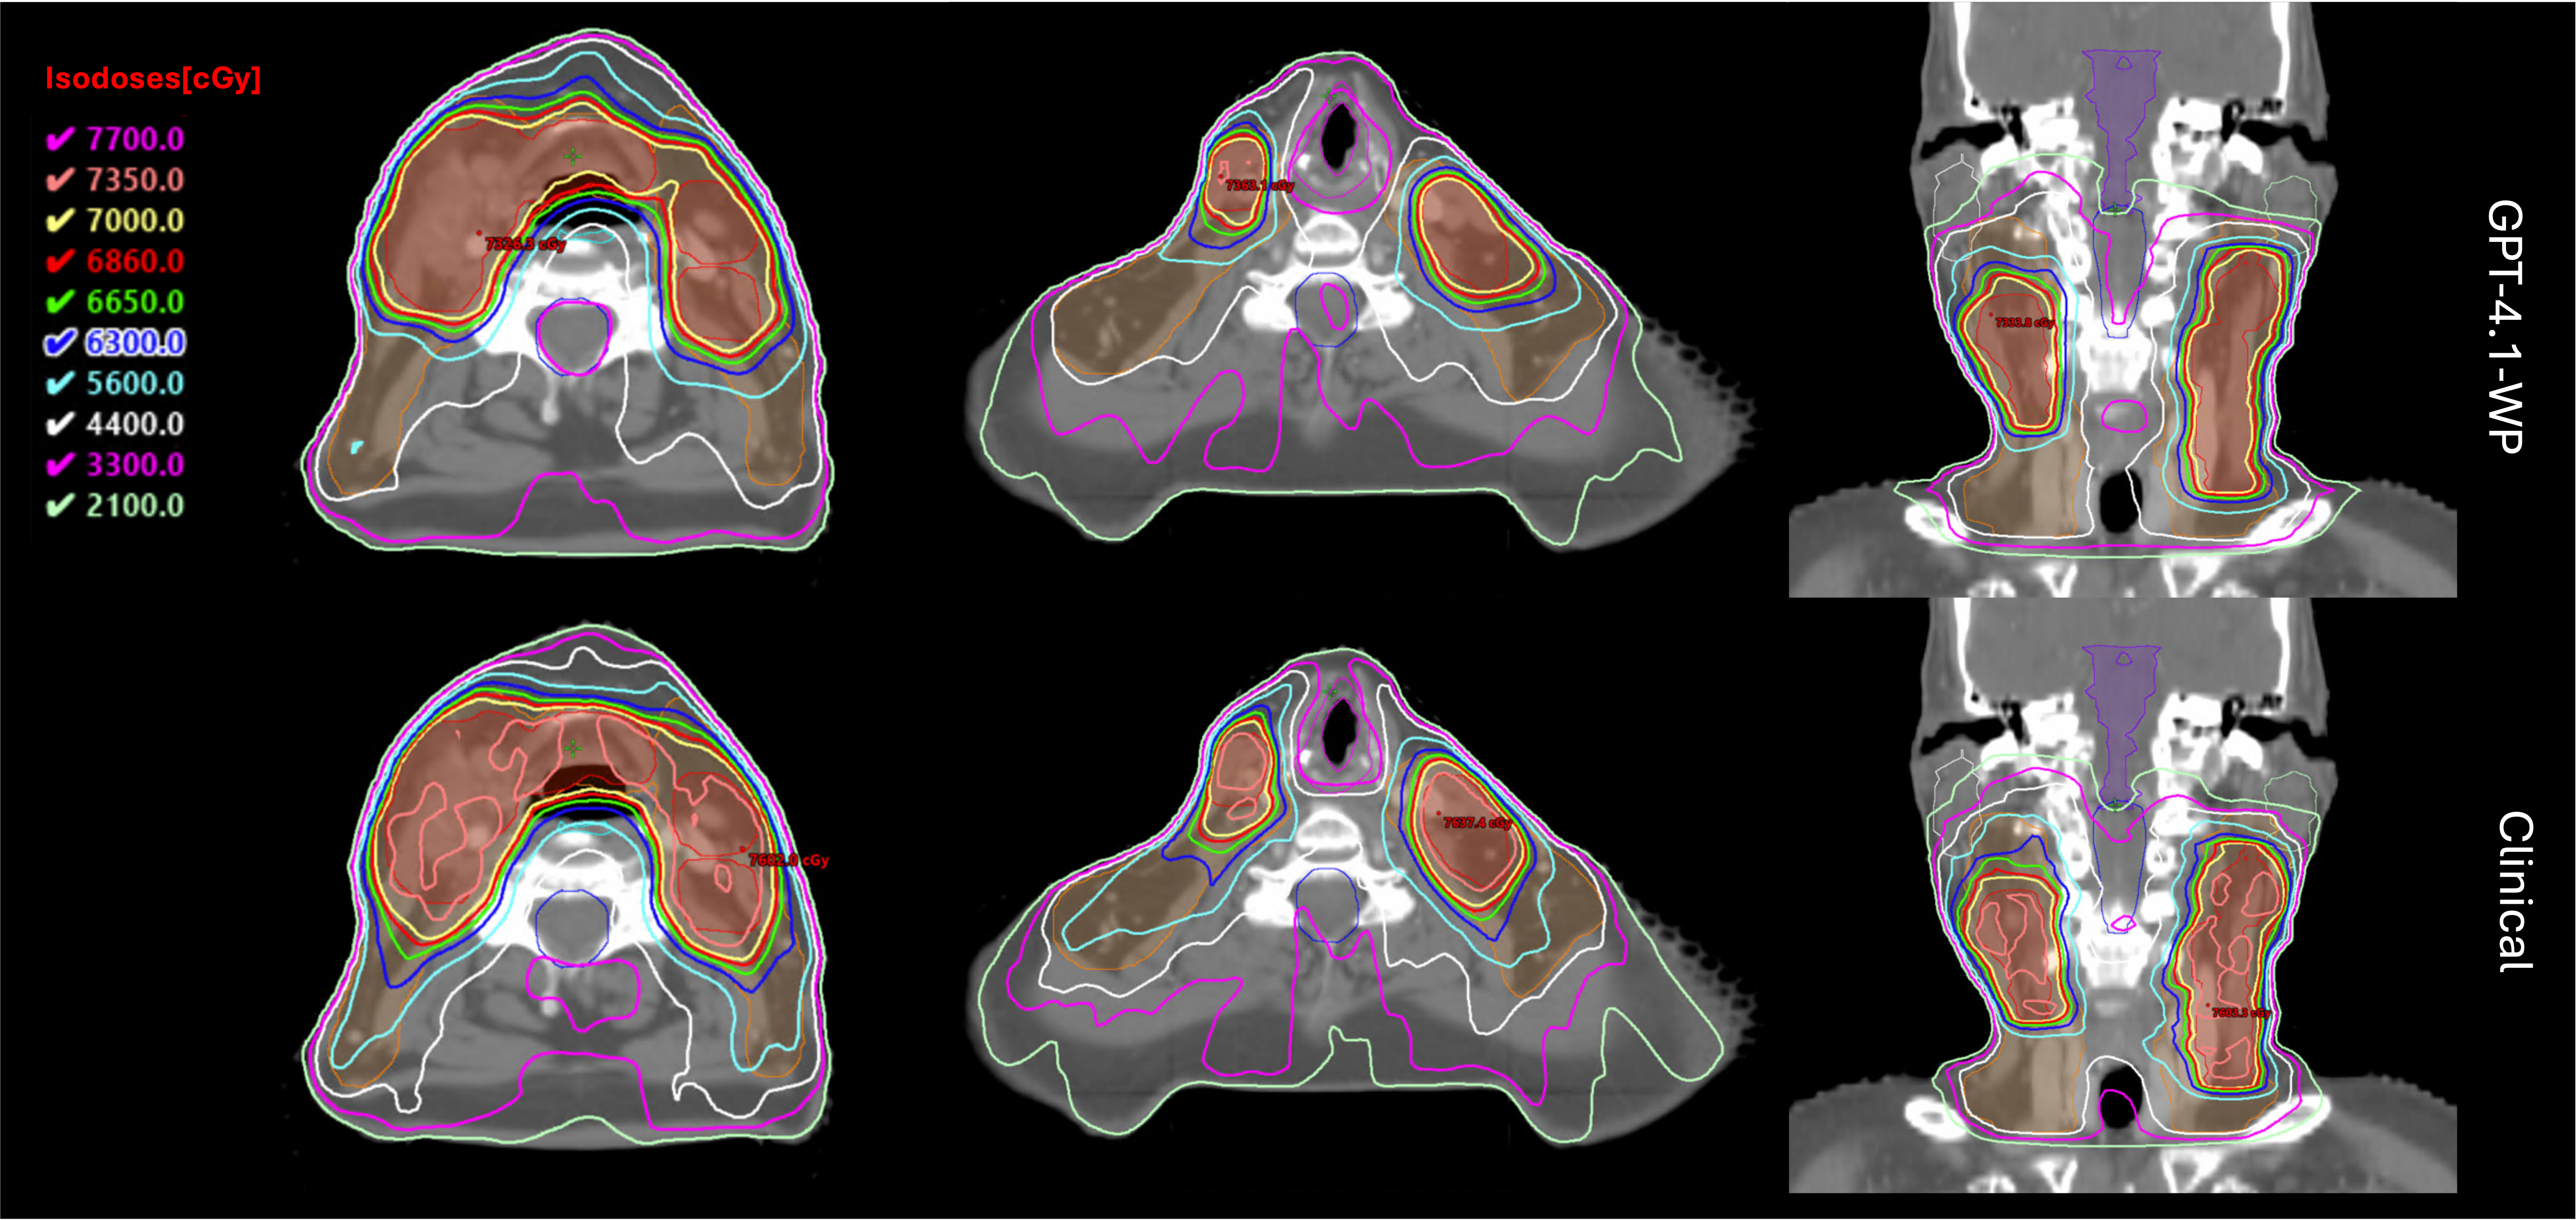

The isodose distribution of the LLM-generated plan and the clinical plan is shown in Figure 4. Both plans achieved adequate coverage of the boost PTV and primary PTV, as evidenced by the 70.0 Gy and 44.0 Gy isodose lines in the axial and sagittal views. In the axial slices of the first column, effective spinal cord sparing is evident in the GPT-4.1-WP plan: the 33 Gy isodose line encircles the cord, highlighting a sharp dose fall-off around this critical structure. A similar pattern of dose fall-off and sparing is observed for the larynx in the axial views of the second column.

In the coronal views (third column), both the LLM-generated and clinical plans demonstrate good conformity of high-dose regions to the target volumes, with the 70.0 Gy and 73.5 Gy isodose lines closely wrapping around the boost PTV. The dose fall-off toward adjacent OARs is well preserved in both plans. In the GPT-4.1-WP plan, the parotid glands exhibit a steeper gradient of intermediate isodose lines, suggesting potential for improved sparing without compromising PTV coverage. Overall, the alignment of isodose lines between the two plans indicates that the LLM agent was capable of reproducing clinically acceptable dosimetric trade-offs. While target coverage was comparable between the clinical and GPT-4.1-WP plans, the LLM-generated plan demonstrated sharper dose gradients around the spinal cord and larynx.

Refer to caption

Figure 4: Comparison of isodose distributions between the GPT-4.1-WP–generated plan (left) and the clinical reference plan (right). Red segment: boost PTV; orange segment: primary PTV.